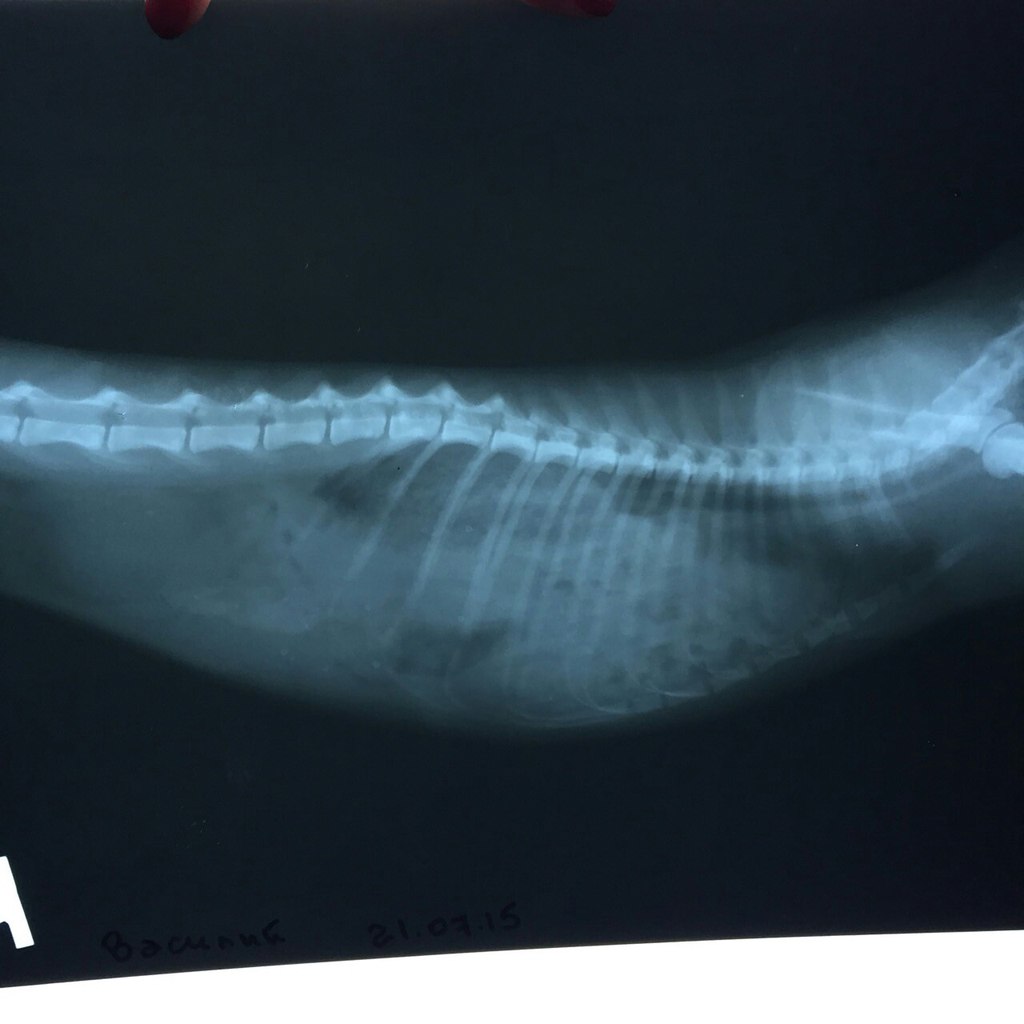

Нажмите на изображение для увеличения

Название: yK0tVq6pibc.jpg

Просмотров: 6

Размер:	132.5 Кб

ID:	10125027Нажмите на изображение для увеличения

Название: DOL2-rrQRqs.jpg

Просмотров: 5

Размер:	98.9 Кб

ID:	10125028Нажмите на изображение для увеличения

Название: mjFziD7RPIE.jpg

Просмотров: 4

Размер:	130.9 Кб

ID:	10125029

На снимках видно сердечко, и все органы на местах)

Девочки, хорошо что вы его отнесли к вету, так бы и не узнал никто, что малышь в такой беде, ведь кошки до последнего не показывают что им плохо, и сложно понять их состояние без нужного обследования, я очень рада за мальчика!